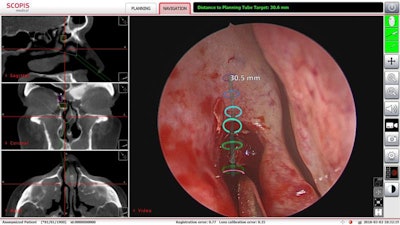

The surgeons used Scopis TGS target-guided surgery technology, which allows for surgical planning from preoperative imaging studies. This planning is overlaid onto the surgeon's endoscopic view of the surgical area, assisting the surgeon in following the defined pathway and avoiding critical structures, according to Memorial Hermann-TMC.